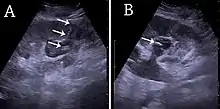

Complex cysts can have membranes dividing the fluid-filled center with internal echoes, calcifications or irregular thickened walls. The complex cyst can be further evaluated with Doppler US, and for Bosniak classification and follow-up of complex cysts, either contrast-enhanced ultrasound (CEUS) or contrast CT is used (Figure 6). The Bosniak classification is divided into four groups going from I, corresponding to a simple cyst, to IV, corresponding to a cyst with solid parts and an 85–100% risk of malignancy.[1] In polycystic kidney disease, multiple cysts of varying size in close contact with each other are seen filling virtually the entire renal region. In advanced stages of this disease, the kidneys are enlarged with a lack of corticomedullary differentiation (Figure 7).[1]

Figure 6. Complex cyst with thickened walls and membranes in the lower pole of an adult kidney. Measurements of kidney length and the complex cyst on the US image are illustrated by '+' and dashed lines.[1] Figure 7. Advanced polycystic kidney disease with multiple cysts.[1]

Figure 7. Advanced polycystic kidney disease with multiple cysts.[1]